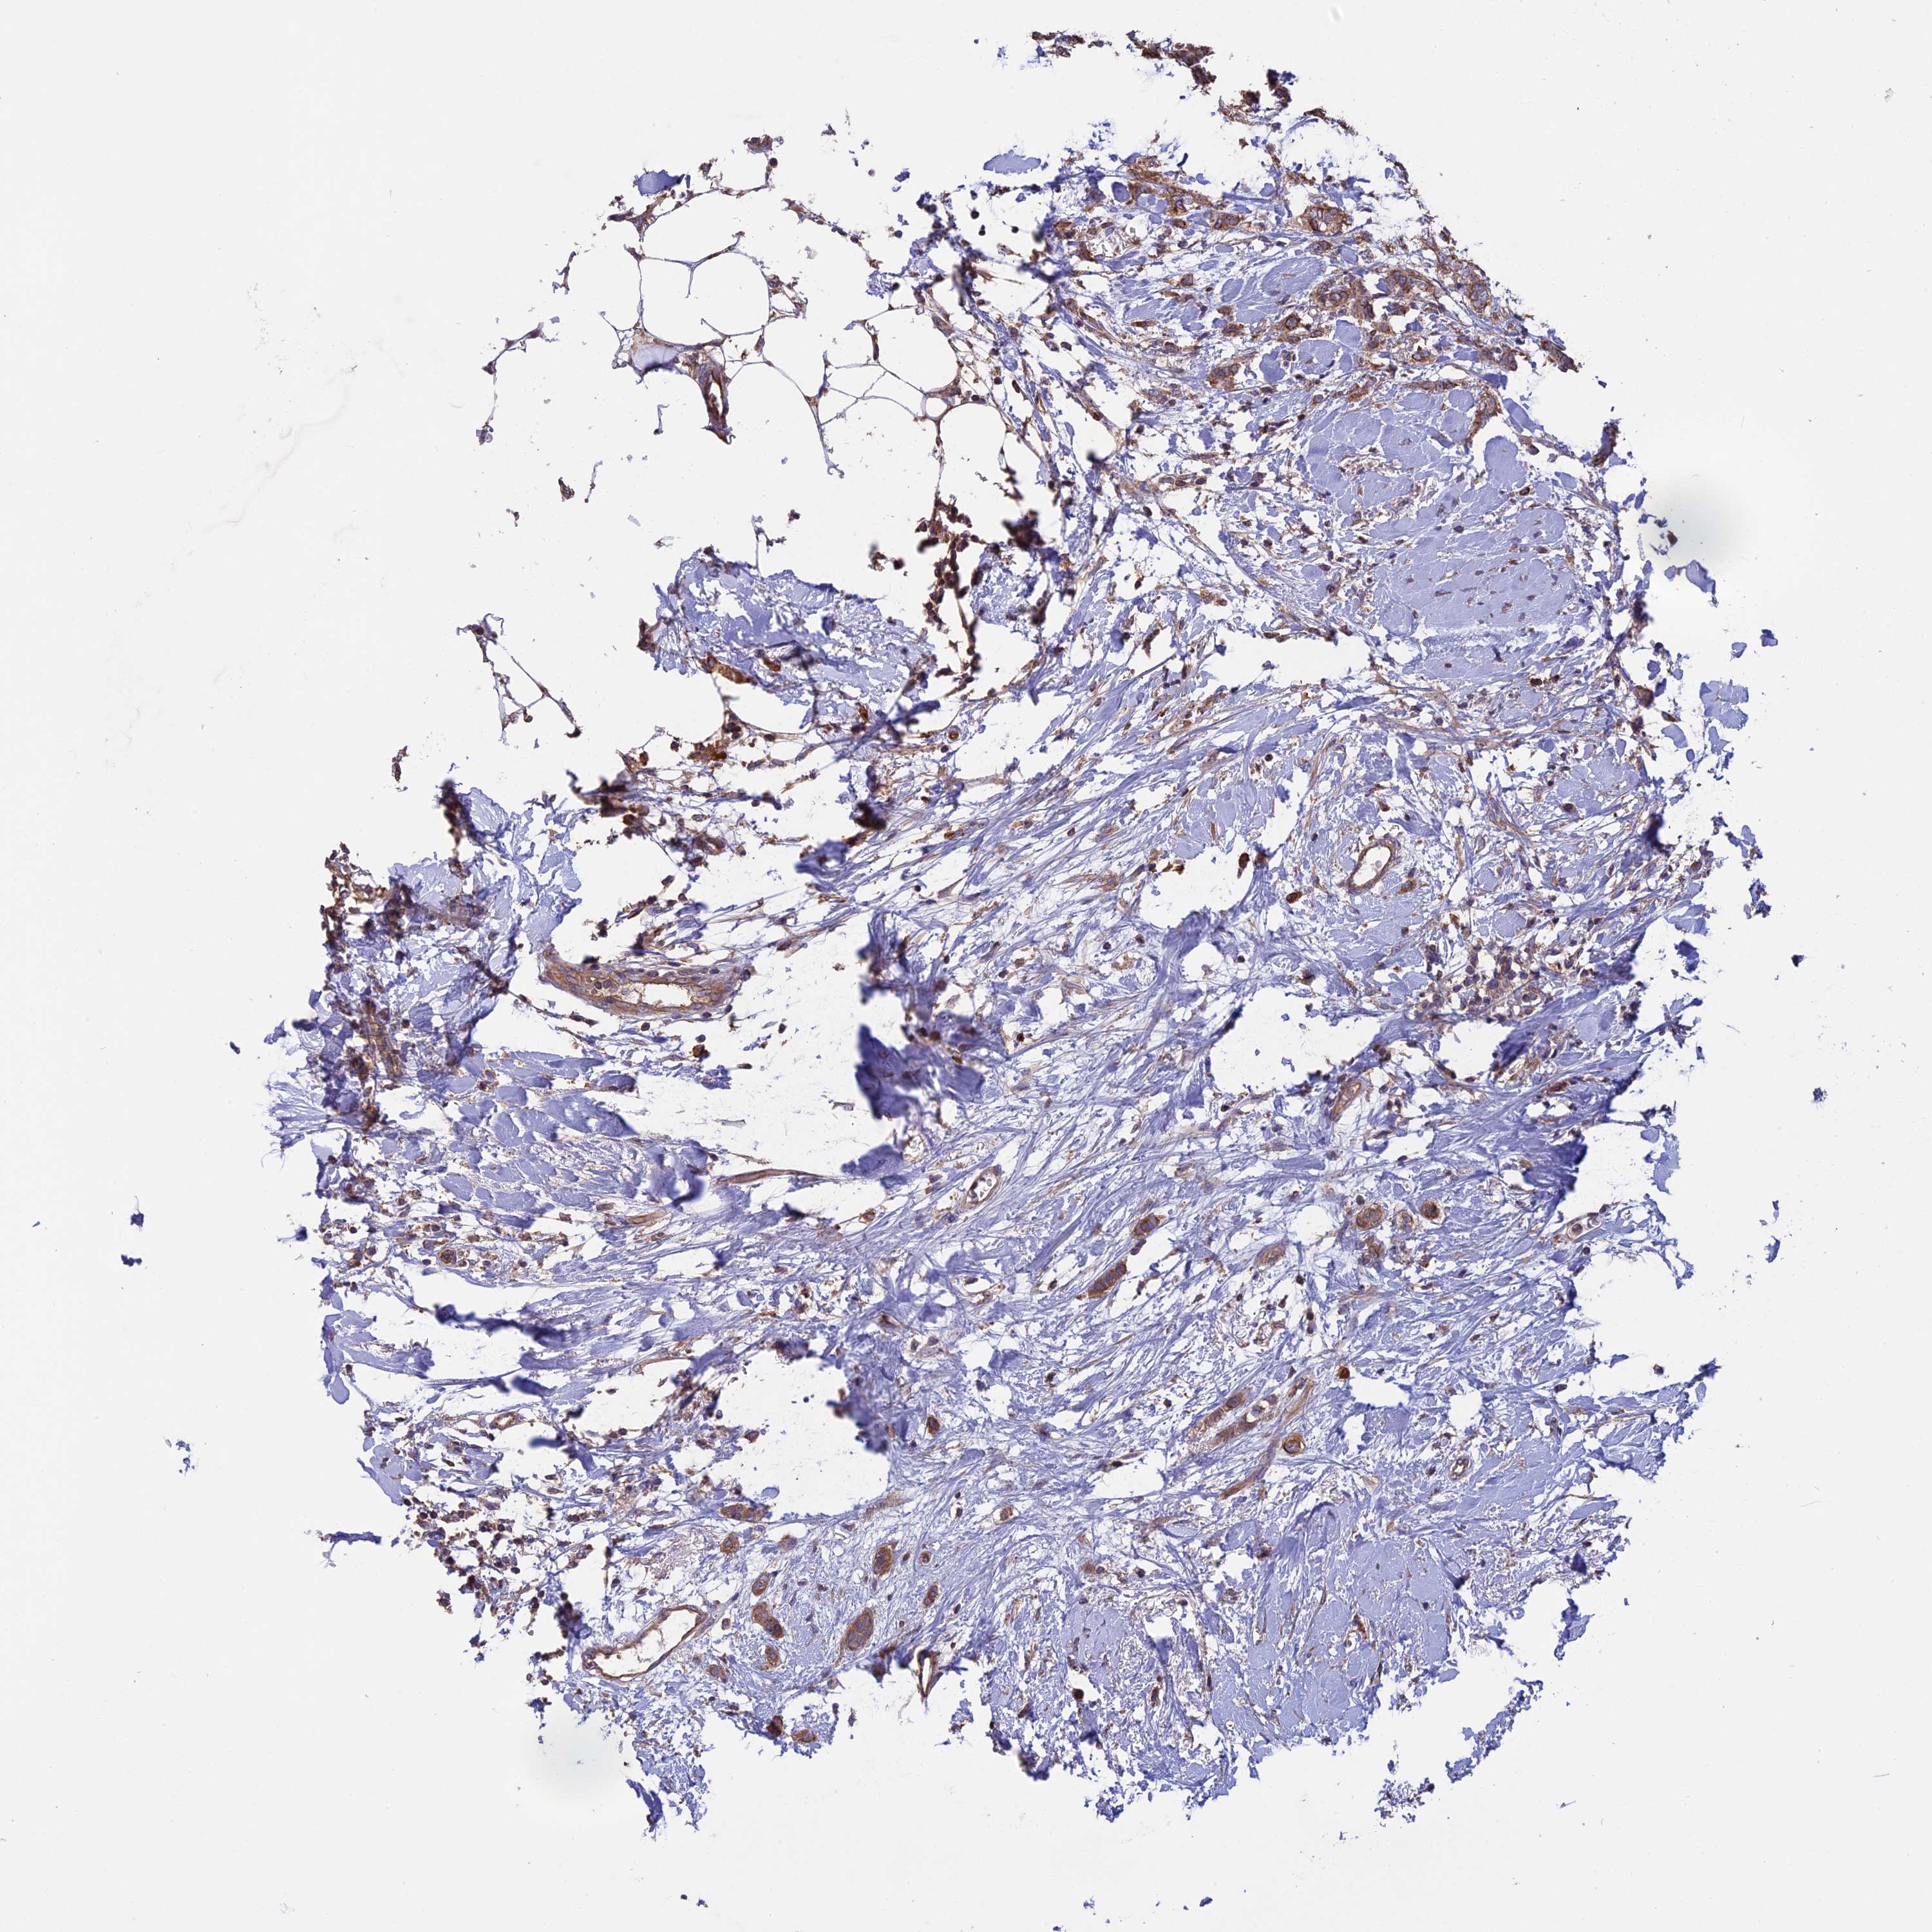

CANCER BREAST CANCER Show tissue menu

BRCA TCGA BRCA VALIDATION PROTEIN EXPRESSION